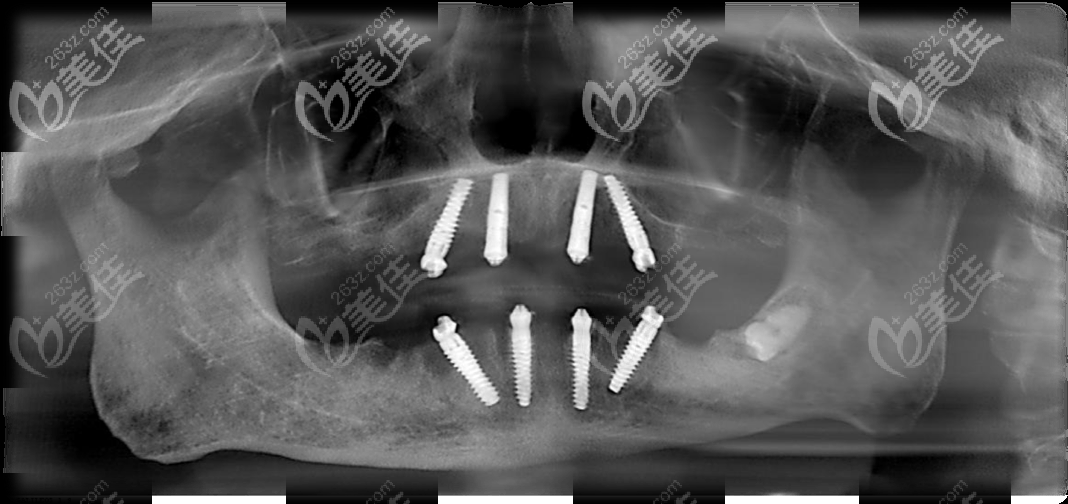

這張是做全口all-on-4種植牙后的CT片

林大爺在馬瀧齒科做的allon4全口種植牙,上下頜各用了4顆種植體;種完當(dāng)天就能啃蘋果哦!